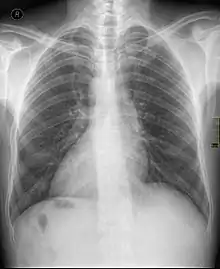

دکستروکاردیا (به انگلیسی: Dextrocardia) یک عارضه مادر زادی است که در آن قلب در سمت راست بدن قرار میگیرد. این عارضه به دو نوع اصلی تقسیم میشود:

این وضعیت بخودی خود مشکلی ایجاد نمیکند و فقط هنگام بررسیهای قلبی مانند نوار قلب باید متوجه آن بود. تقریبا از بین هر ۱۲۰۰۰ نفر یک نفر دچرا همچین عارضهای می شود.